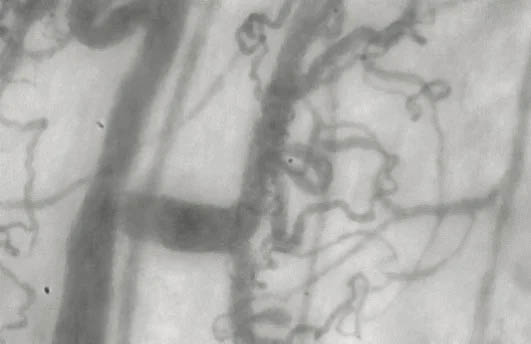

Microvascular Capillaries Before & After Taking Endocalyx*

Unhealthy microcirculation (before)

Month 0 – BEFORE taking Endocalyx

Low Microvascular Health Score = 0.6

Healthy microcirculation (after)

Month 0 – AFTER taking Endocalyx

High Microvascular Health Score = 3.9

These before and after images were captured by the GlycoCheck micorvascular testing system. GlycoCheck analyzes capillaries that are as small as 4 microns, so small that about a 100 of these tiny capillaries fit inside a human hair.

*Results will vary based on each individual patient. GlycoCheck is a monitoring device and not intend to diagnose any disease.